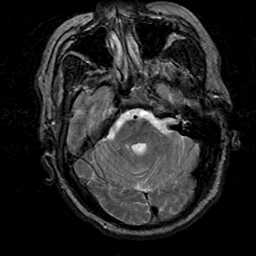

Subacute Stroke, overlay -- Slice #6

[Home][Help][Clinical] Slice 6